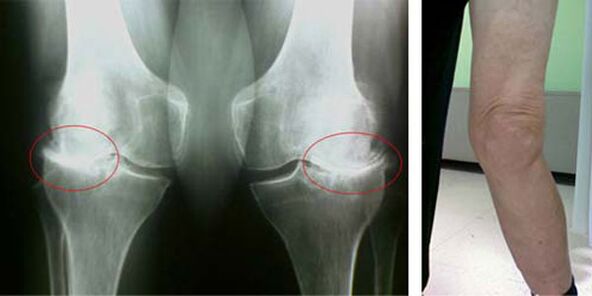

Die Anfangsstadien des Auftretens einer solchen Pathologie wie Arthrose des Kniegelenks manifestieren sich in keiner Weise visuell. Nach einer gewissen Zeit bemerkt der Patient jedoch Anzeichen einer Kniedeformität sowie eine charakteristische Krümmung entlang der Achse des Unterschenkels (nach innen gerichtet). Es gibt auch ein Knirschen, wenn Sie das Bein beugen müssen.

Das Vorhandensein von Schmerzen und eingeschränkter Bewegung im Knie veranlasst eine Person, einen Arzt aufzusuchen und sich einer Untersuchung zu unterziehen. Dazu muss er Tests bestehen und eine Röntgenaufnahme des erkrankten Gelenks machen. Reichen diese Maßnahmen nicht aus, um eine Arthrose des Kniegelenks nachzuweisen, wird eine Magnetresonanztomographie durchgeführt. Anhand der gesammelten Daten wählt der Arzt die besten Behandlungsmethoden aus.